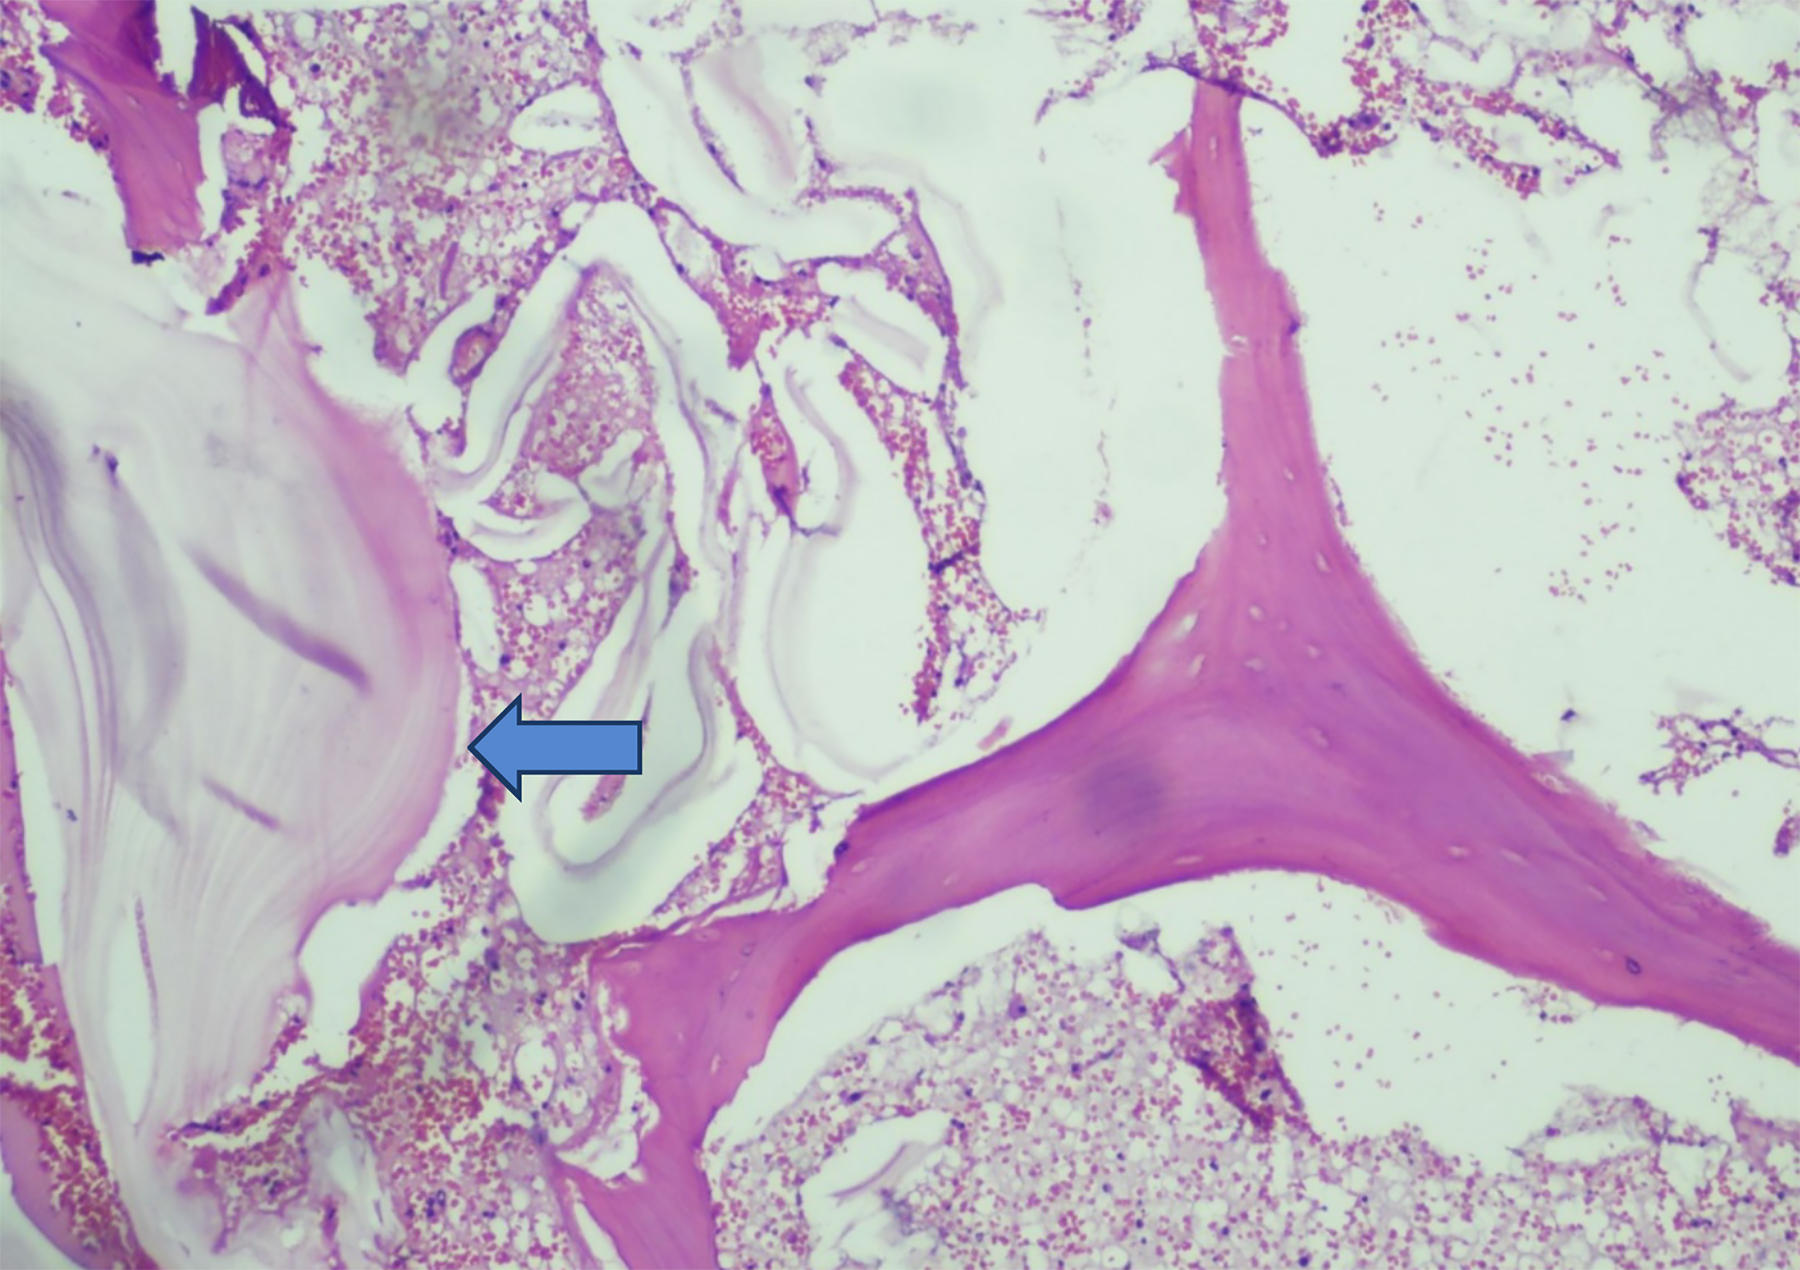

Histopathological examination of the excised tissue revealed the presence of laminated membranes and scolices (Figure 1), confirming the diagnosis of a hydatid cyst. The cyst wall exhibited a characteristic three-layered structure: an outer fibrous capsule, a middle layer containing a laminated and acellular material, and an inner germinal layer with protoscolices (Figure 2). These findings are crucial for differentiating hydatid disease from other cystic lesions.

Figure  2:  High-power view showing the germinal layer with protoscolices present adjacent to bone trabeculae.